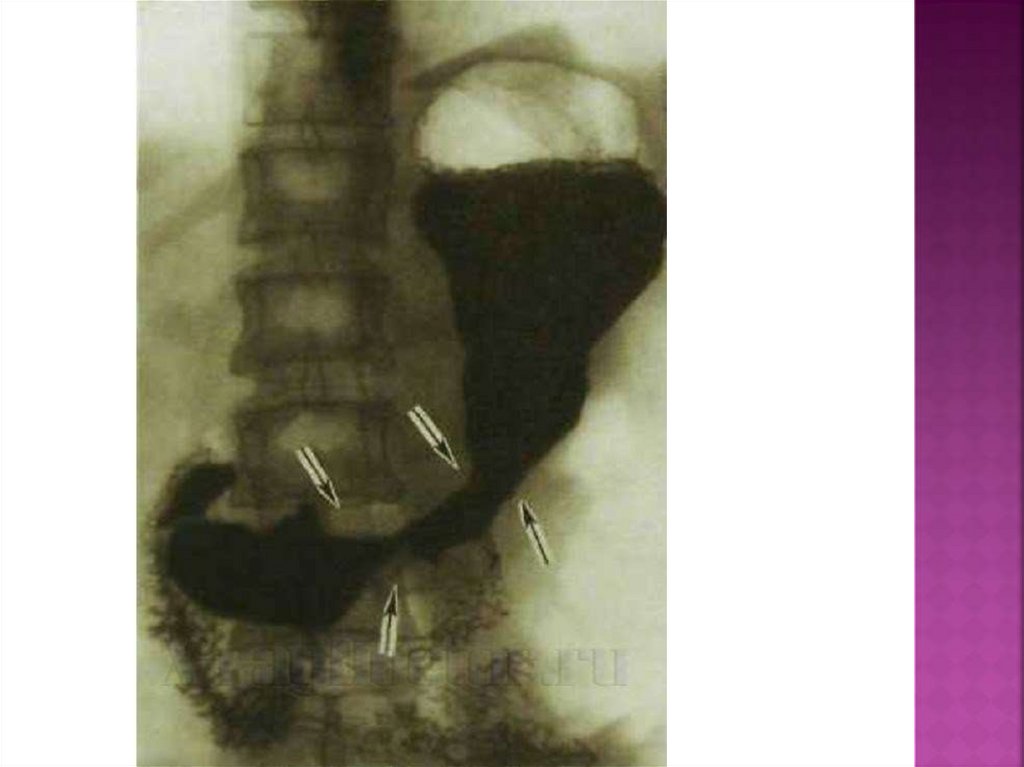

-рентгенологическое исследование

(контрастирование жкт с барием)